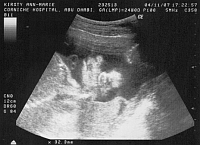

Scan at 36 weeks - Basil

is lying sideways and you can see it's eyes and mouth and the fingers of

it's right hand which is on it's head, and left hand below it's face.

It's lying sideways in my tummy with it's head down getting ready to go

apparently.